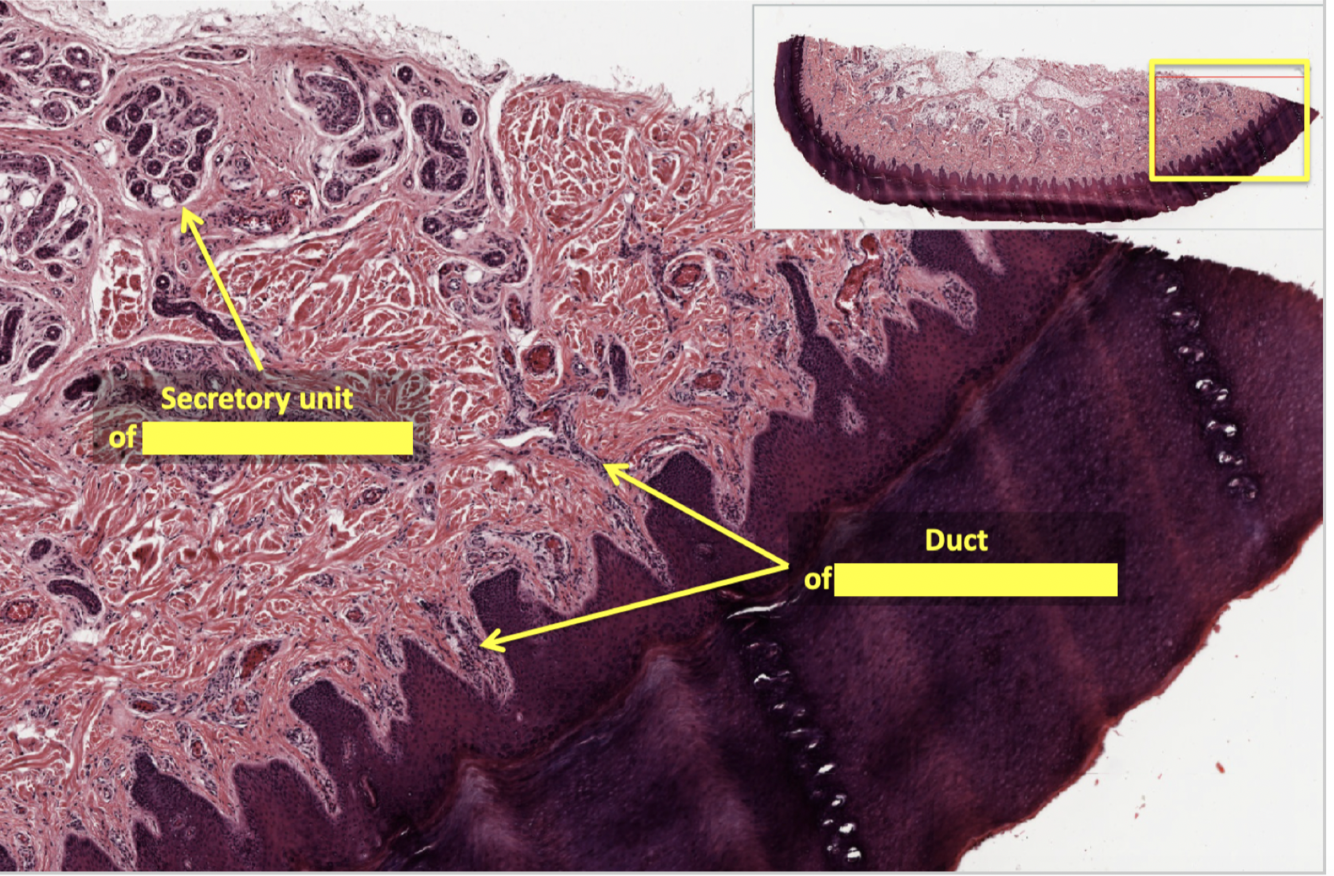

sweat gland ducts have what kind of epithelium

in what layer of the skin are sweat glands located

role